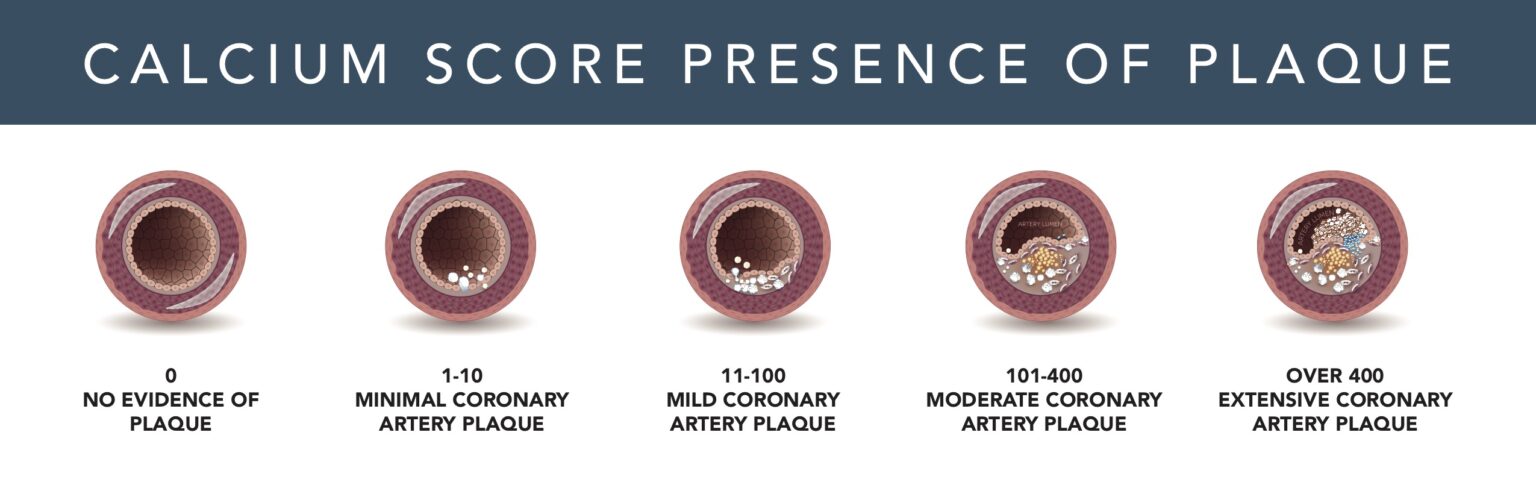

How Does Your Heart Score? - Consulting Radiologists

www.consultingradiologists.com

www.consultingradiologists.com

calcium coronary artery calcification plaque amount scanner

What Is A Good Coronary Artery Calcium Score

What Is A Good Coronary Artery Calcium Score